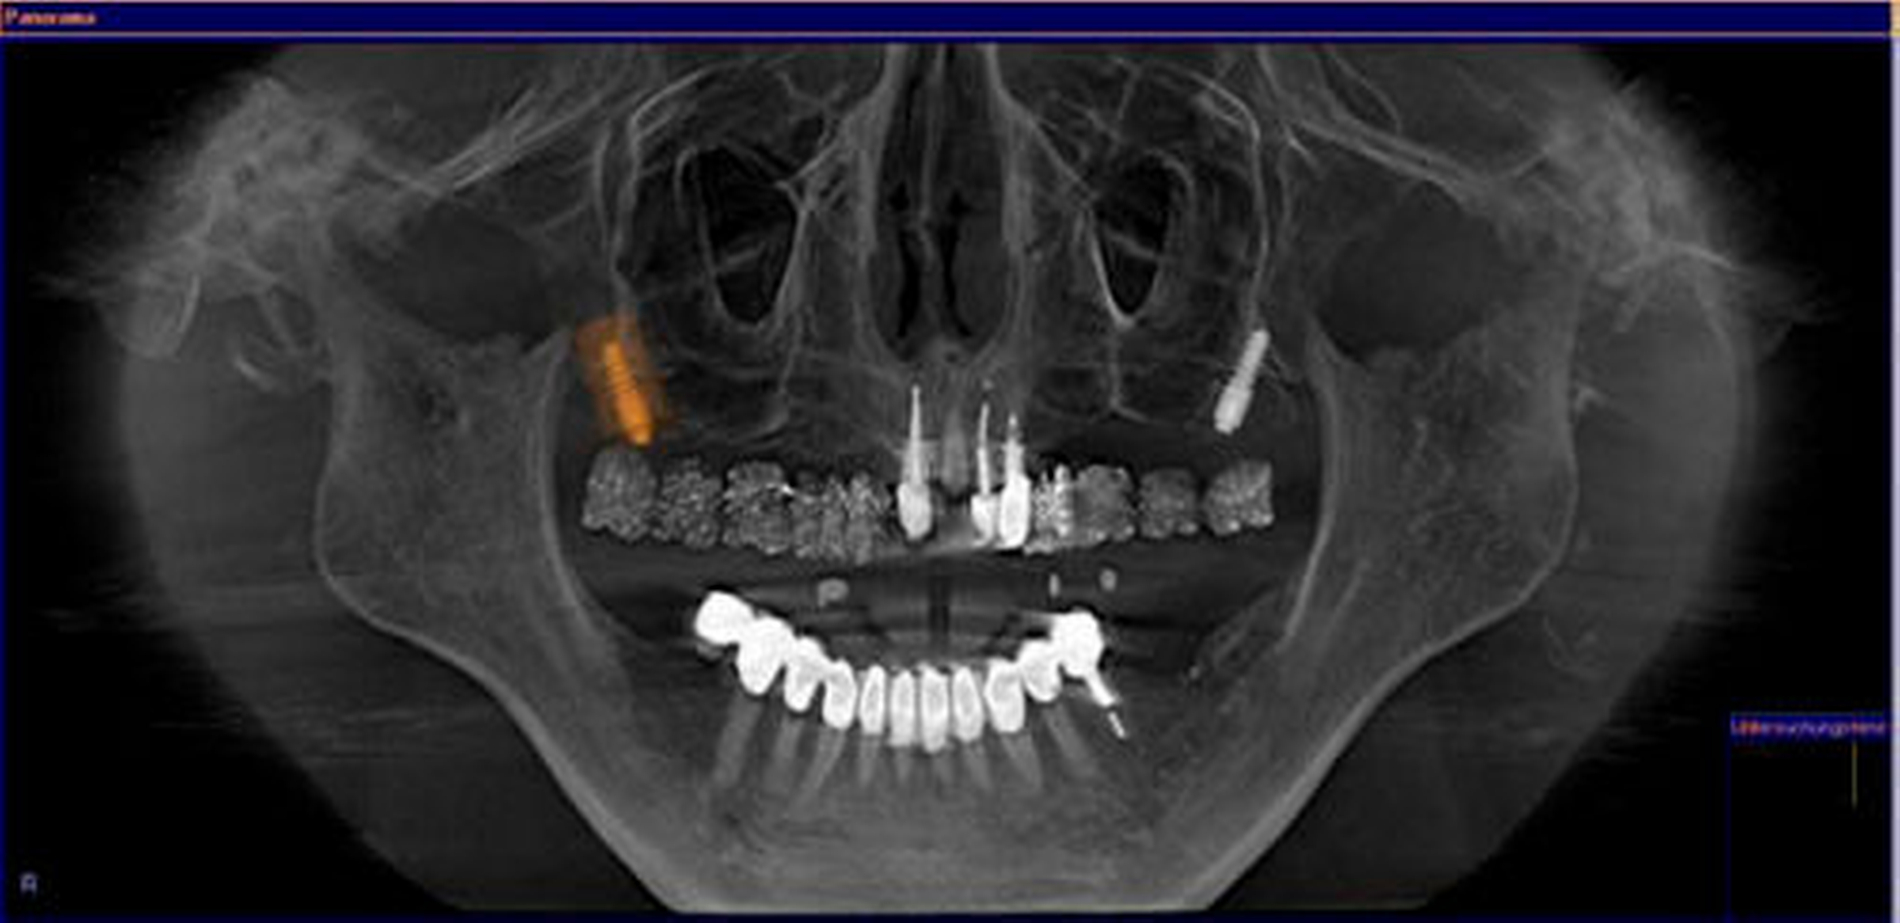

Sowohl die drei- als auch die zweidimensionalen Darstellungen der Hauptebenen ermöglichen eine einfache Orientierung; sie orientieren sich aber nicht direkt an der Anatomie. Einen wesentlichen Vorteil bietet dagegen die Darstellung von gekrümmten Oberflächen. Auf diese Weise können Ansichten aus den DVT-Volumendaten synthetisiert werden, die senkrecht auf der in der Transversalebene festgelegten Mittellinie durch den Kiefer stehen. So erhält man Ansichten, die dem Bildeindruck einer Panoramaschichtaufnahme (PSA) gleichen. Überlagerungsfreie Abschnitte lassen sich in jedem beliebigen Bereich des Aufnahmevolumens in einem separaten Befundungsfenster (dem sogenannten „inspection window“) bündeln, was eine exakte Diagnostik auch kleinster pathologischer Läsionen ohne störende Überlagerungsartefakte ermöglicht (Abbildung 4).

In den letzten Jahren hat die Bedeutung der 3D-Bildgebung für die präimplantologische Diagnostik zugenommen [Besimo et al., 1998; Krat, 1998]. Durch die DVT-Diagnostik steht eine Vermessungsoption zur metrischen Analyse zur Verfügung. Da die Darstellung der Schicht bereits metrisch kalibriert wurde, ist es im Gegensatz zur PSA nicht notwendig, eine Referenzkugel zur Kalibrierung zu verwenden. Mit der Messfunktion kann das Knochenangebot in horizontaler und vertikaler Dimension bestimmt werden. Ebenso ist es wichtig, bei der Planung die genaue Position der prothetischen Versorgung zu kennen. Hier kann entweder eine klassische Bohrschablone mit vom Zahntechniker eingebrachten Bohrhülsen oder eine Röntgenschablone zum Einsatz kommen. In der Röntgenschablone wird der prothetische Vorschlag des Zahntechnikers röntgenopak in bariumsulfathaltigem Kunststoff umgesetzt (Abbildung 7) [Zöller, 2007].